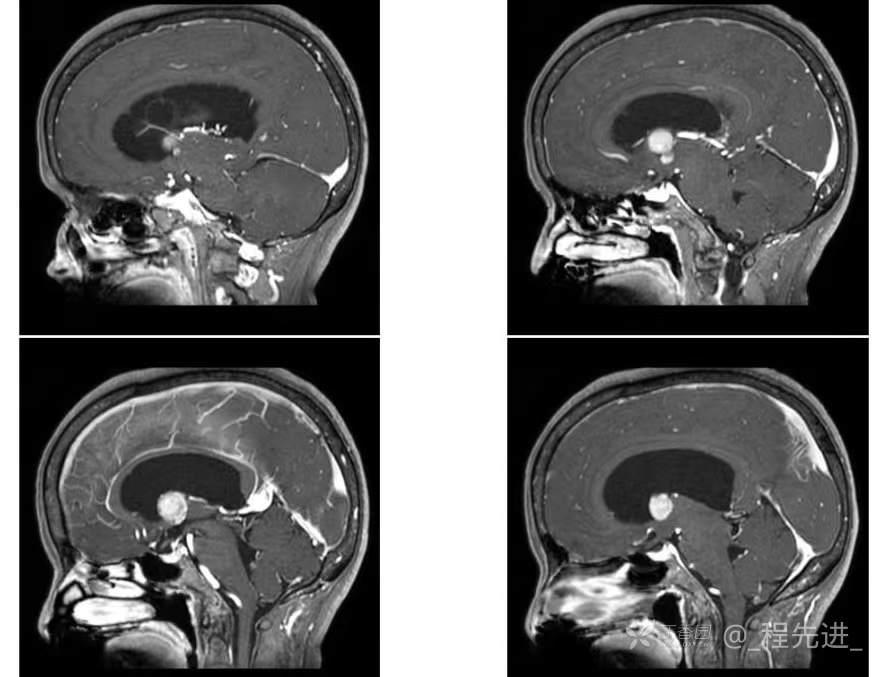

患者性别:女

患者年龄:55岁

简要病史:头痛头晕4年余,无明显诱因,10余年前因“输卵管破裂大出血”手术治疗

脑膜瘤 (78)

过渡型(混合性)脑膜瘤 (1)